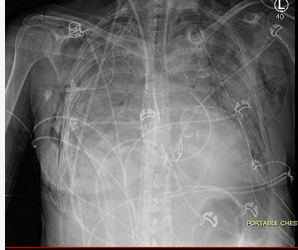

Twenty-four hours later, the patient now develops worsening oxygenation and requires reintubation. There was no witnessed aspiration before this event. There are new bilateral alveolar opacities on a chest radiograph (Figure 1). Vital signs are a temperature of 37.2 °C, pulse of 100/min, and BP of 120/70 mm Hg. SpO2 is 90% with FIO2 of 0.6 and PEEP is 8 cm H2O. Pulmonary artery occlusion pressure is 11 mm Hg. Arterial blood gas measurements are a pH of 7.38, PCO2 of 42 mm Hg, and PO2 of 70 mm Hg. Current medications include methylprednisolone, tacrolimus, mycophenolate mofetil, vancomycin, piperacillin-tazobactam, ganciclovir, posaconazole, and trimethoprim-sulfamethoxazole. There have been no additional blood transfusions. The brain-type natriuretic peptide (BNP) level is normal, and BAL cultures are negative to date. Results of a bedside transthoracic echocardiogram are unremarkable.